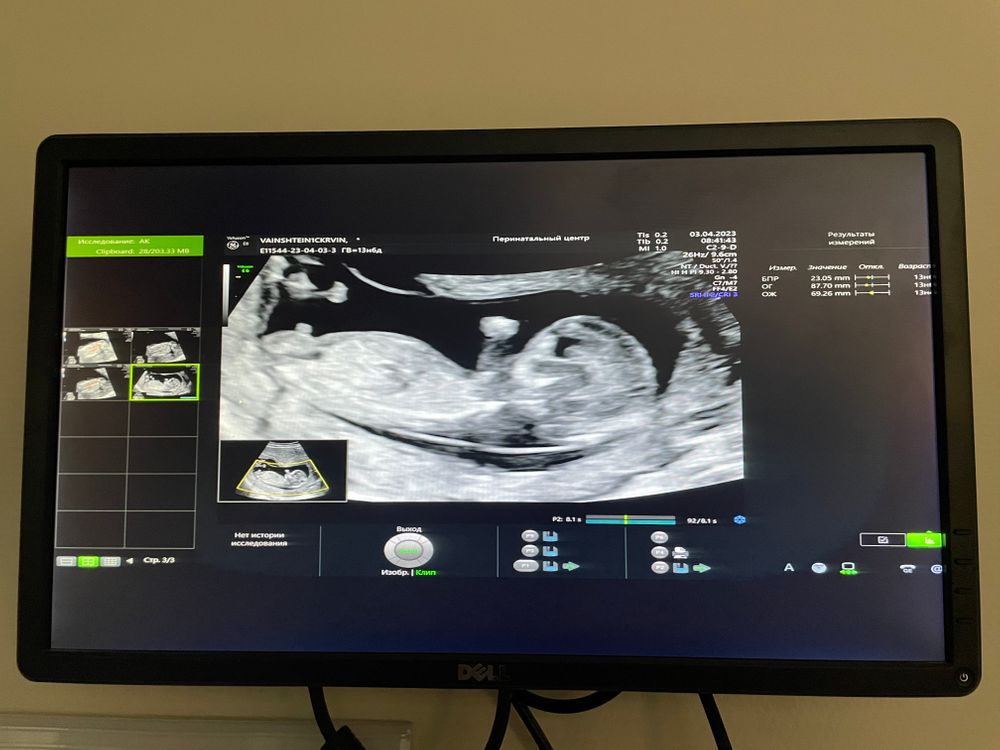

Я вижу голову и живот)) как по ним определить пол я хз🤣

Профиль ребёнка

Тут не видно и рано

Изображение Это мой сынок😁

Малинка, тут спрятано причинное место )

Девчуля

елена, проверим в 16 недель ) на снимке тоже кажется что девочка , а по видео 100% мальчтк ))) не знаю где плоскость изображения верная , вроде везде одинаково лежит

У вас девочка.

Профитроль, проверим в 16 недель ) по видео я увидела только мужскую пипку кверху задранную . Интересно какой срез был более достоверный ))

Девочка)

Тут нет этого участка))) как сказала узист ждите второго скрининга 😄 слава богу, я сдала кровь на определение 🙌

Саша, мы пойдём в 16-17 недель смотреть пол )

Саша, ой пипку видно ага )) но на видео мне тоже показалось что пипка мужская мелькает )))